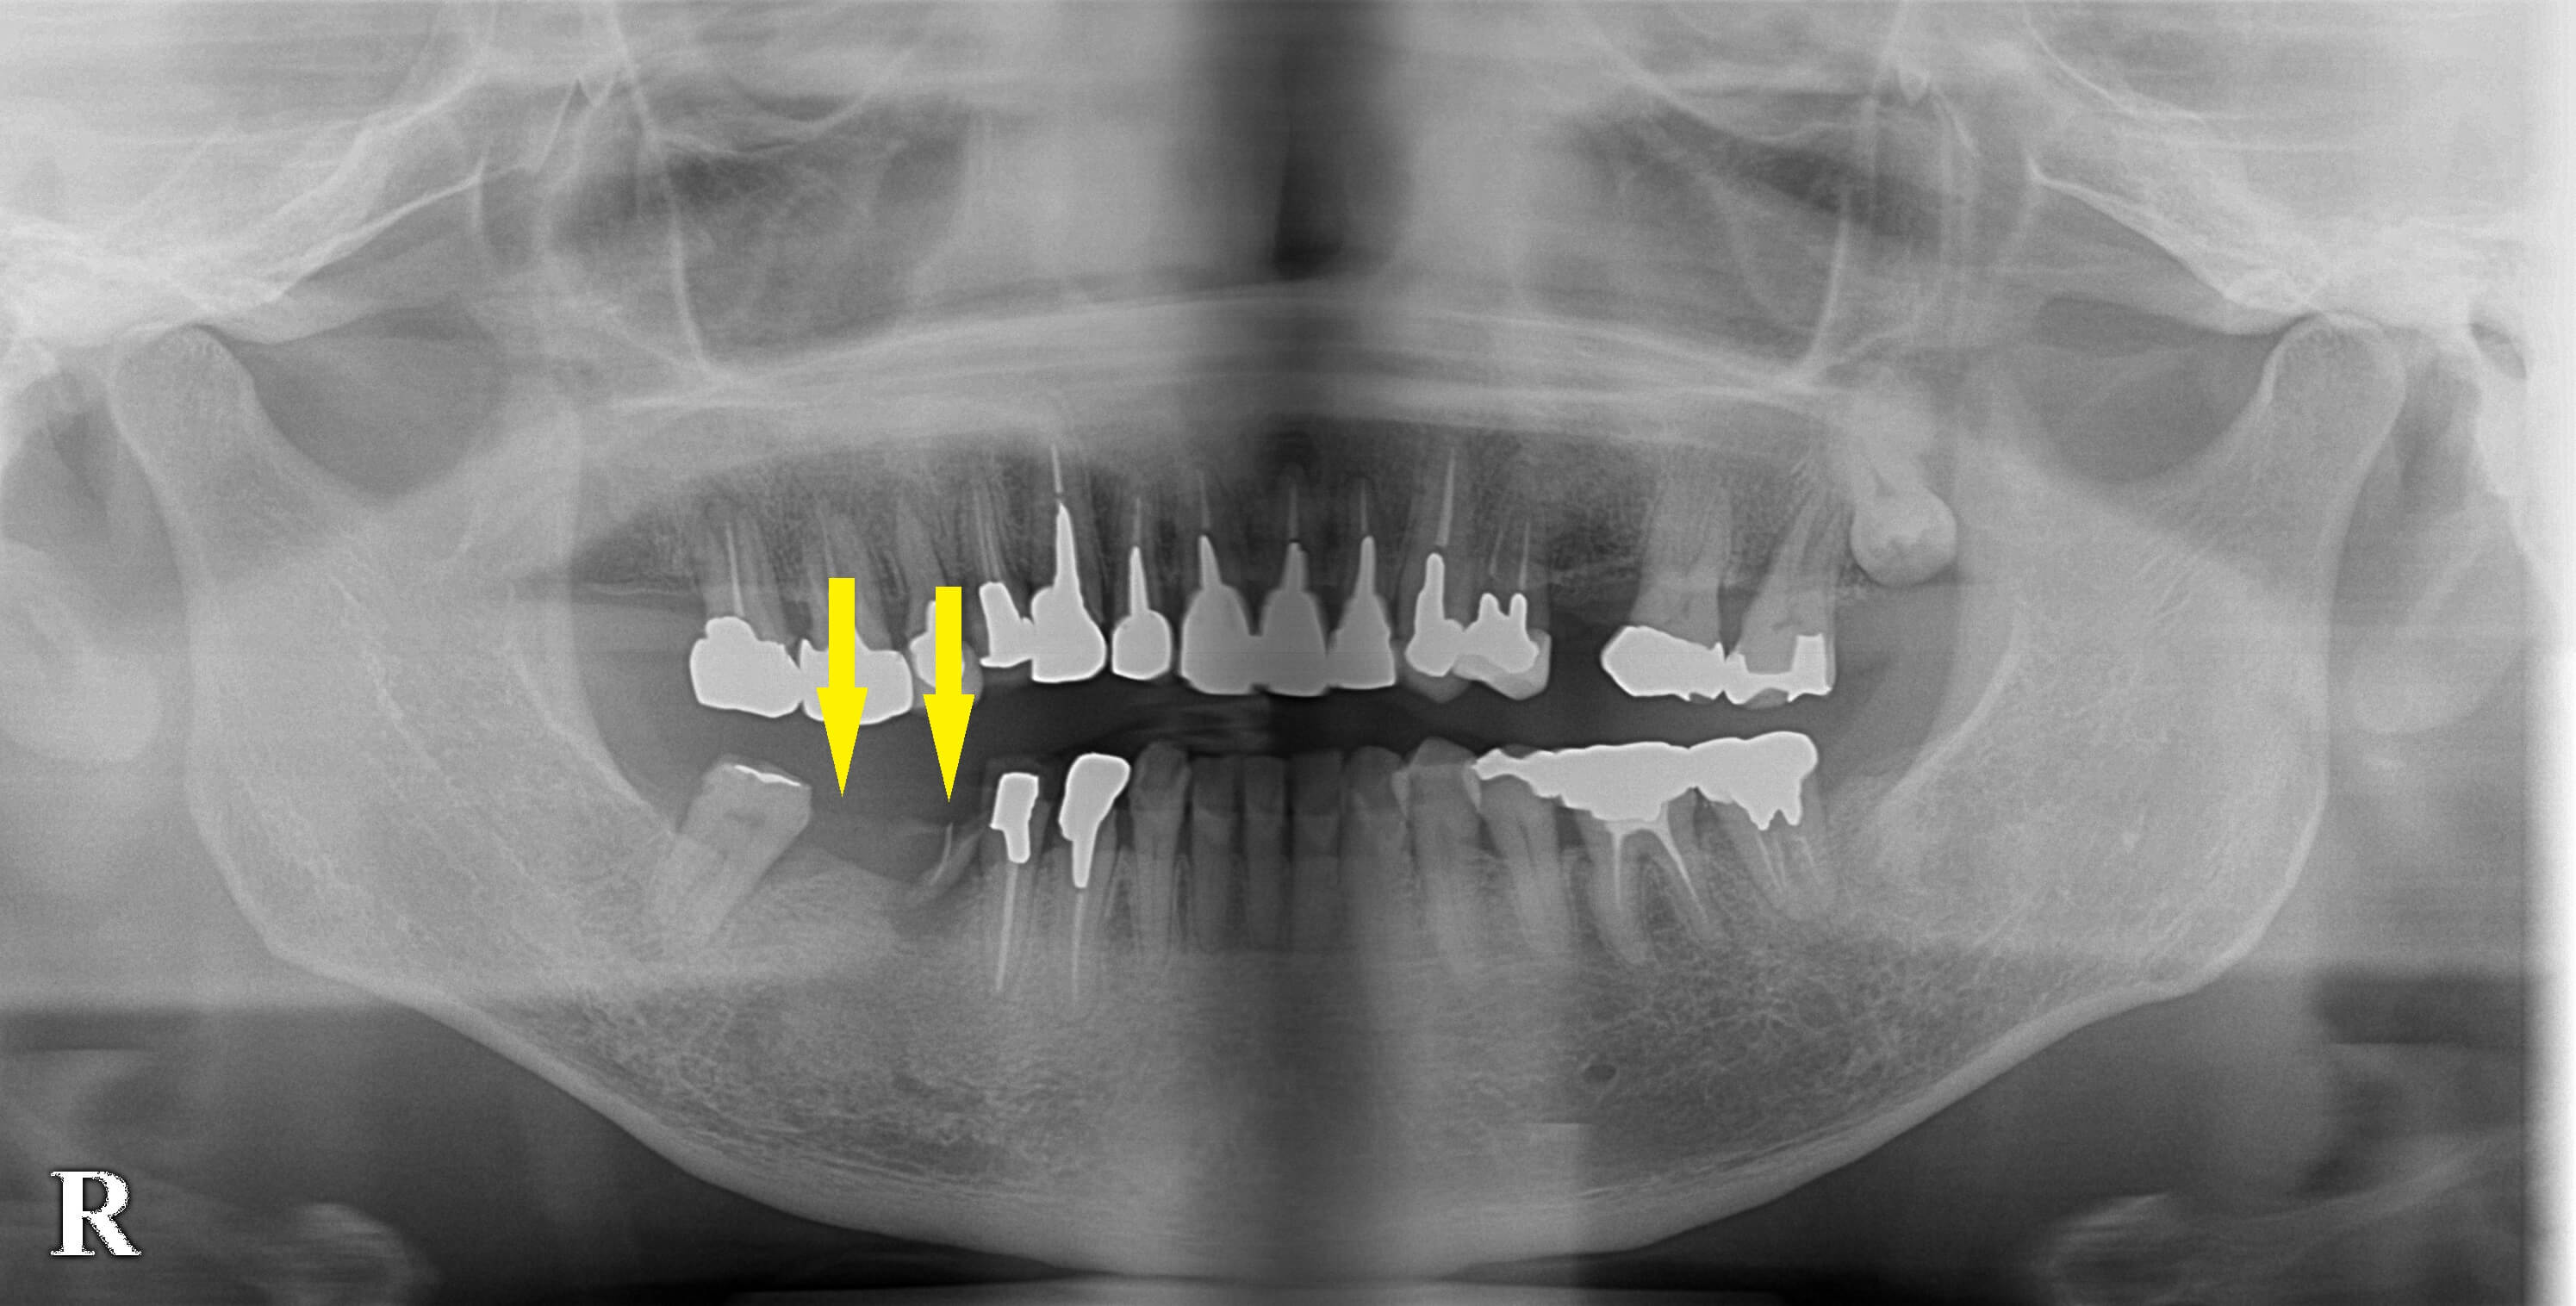

右下顎に装着されていたブリッジの、前方の支えになっていた歯が折れてしまいブリッジが外れてきたそうです。

骨の量は問題ありませんでしたので、折れた歯は抜歯し治癒を待って、抜歯した部位とその後方に、2本のインプラント埋入術を行いました。

ブリッジの支えになっていたもう一方の歯は保存し冠を被せ直しました。